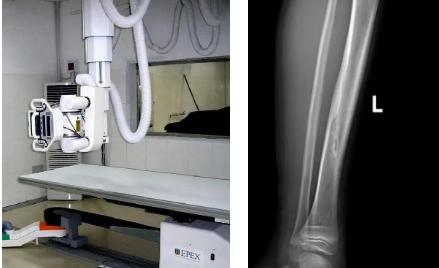

一般骨科創(chuàng)傷的病人,只要到影像科拍一張X光片,很快就會明確診斷有沒有骨折。然而有一些特殊類型骨折的病人,由于拍片影像重疊的緣故,或者骨折未發(fā)生明顯移位,病變可能顯示不出來,等過了一段時間后,骨折部位才能夠顯示清楚。這種類型的骨折,叫做隱匿性骨折。若在臨床上診斷及時且明確,及時固定患者的骨折部位,進行適當(dāng)治療并減少運動,對患者的恢復(fù)有重要意義。

1.定期復(fù)查。一般于骨折后2-4周,骨折進入骨痂期,骨折斷端有新生骨形成,呈明顯高密度,無論是X線或是CT,都能比較清晰觀察到,通過前后圖像對比,較容易診斷隱匿性骨折。

2.CT或MRI檢查。CT是斷面成像,不會出現(xiàn)重疊而導(dǎo)致漏診,同時CT還可以進行多平面的重建,除了發(fā)現(xiàn)X線無法發(fā)現(xiàn)的骨折外,還可以三維直觀的顯示骨折的程度,對臨床治療有指導(dǎo)意義。CT無法發(fā)現(xiàn)骨裂、不全骨折或者骨挫傷,對軟組織的損傷診斷也有局限性,MRI就可以發(fā)現(xiàn)這些損傷。